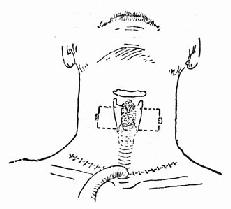

4.手术方法 ①颈部低位横切口行常规气管切开术(图96-10)。②常规喉裂开术(图96-11)。直视下仔细缝合喉粘膜裂口(96-12)。置入事先准备好的喉扩张模(牙模胶或硅橡胶制成)放入喉腔,扩张模下界在环状软骨水平,上界在室带水平即可,用金属线固定此扩张模。金属线穿过甲状软骨板和皮肤后,用钮扣固定在颈部皮肤表面(图96-13)。尽量对合复位甲状软骨板,并缝合甲状软骨板外软骨膜,逐层缝合切口(图96-14)。③手术后使用强有力的抗生素控制感染。按气管切开术后护理。④6~12周后直接喉镜下取出喉扩张模。⑤取模后试行堵管,无呼吸困难后可拔除气管套管。

图96-10 颈部低位横切口气管切开

图96-11 喉裂开术

图96-12 直视下缝合喉粘膜裂口

图96-13 置入扩张模并固定之

图96-14 逐层缝合